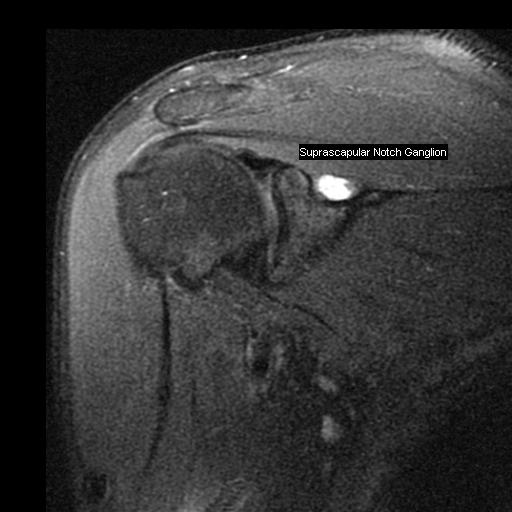

Figure 1 for case Notch ganglion cysts

Figure 1